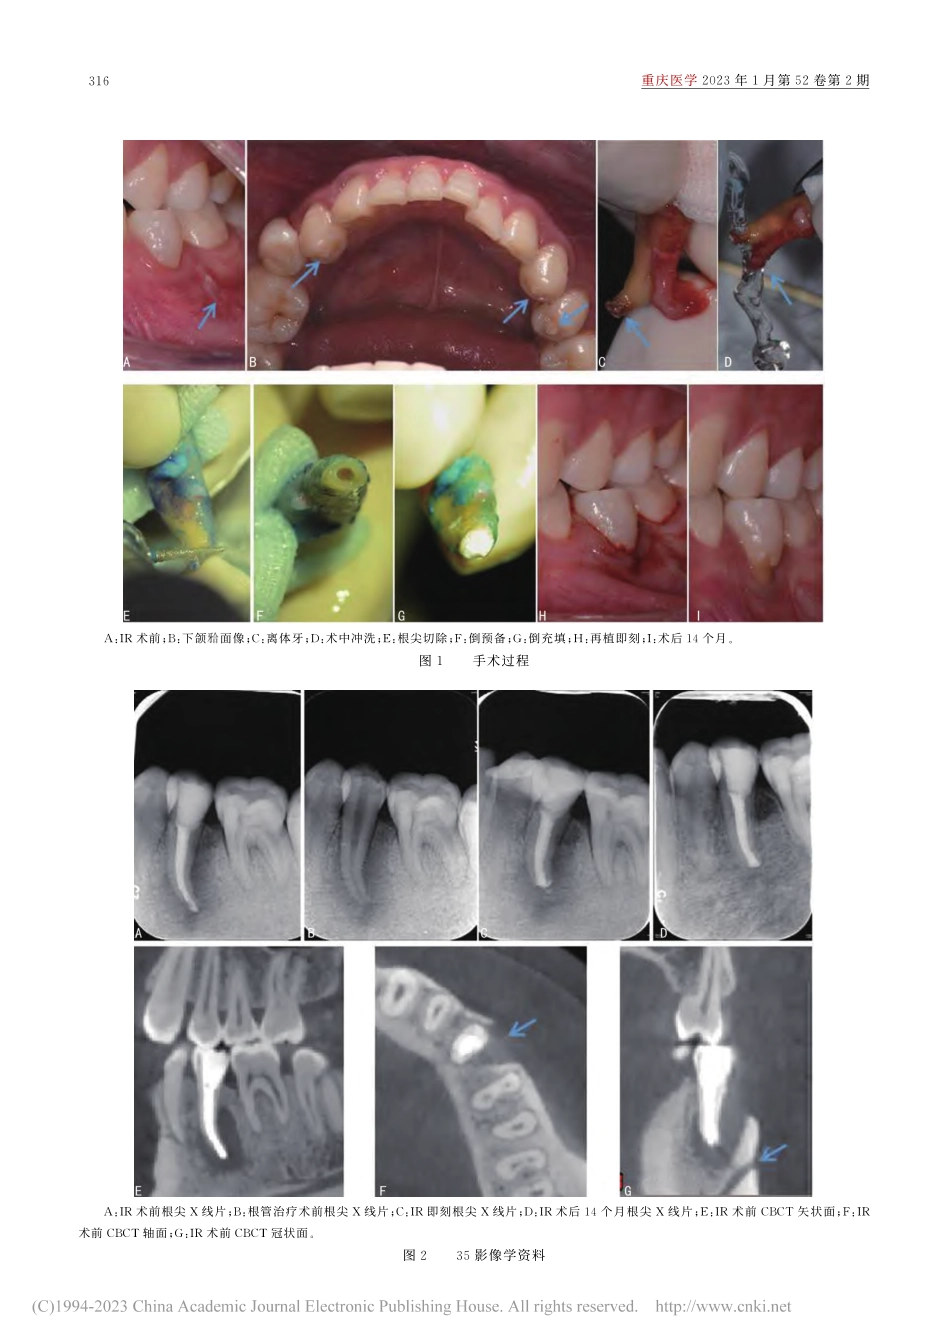

·短篇及病例报道·doi:10.3969/j.issn.1671-8348.2023.02.031网络首发https://kns.cnki.net/kcms/detail//50.1097.R.20230113.1103.002.html(2023-01-13)意向性牙再植术治疗左下第二前磨牙慢性根尖周炎1例*孙琼1,胡晓蕾2,沈正焱1,管理霞1(合肥市口腔医院:1.牙体牙髓二科;2.综合科230001)[关键词]畸形中央尖;颏孔;意向性牙再植术;根尖外感染;根尖囊肿[中图法分类号]R781.34[文献标识码]B[文章编号]1671-8348(2023)02-0315-04意向性牙再植术(intentionalreplantation,IR)的临床病例最早见于11世纪,之后陆续有相关的病例报道。近年来,随着牙科手术显微镜(dentaloperativemicroscope,DOM)在牙体牙髓病学的广泛应用,显微根管外科理念的更新和生物材料的发展,显微IR这项技术也日趋成熟,有研究报道2006年后的成功率已达到90%以上[1]。该治疗方法适用于已行完善根管治疗/根管再治疗或无法行根管再治疗的患牙出现或持续根尖周炎症,部分患牙由于手术进入路径困难或解剖位置限制,亦或有的患者由于自身原因不能配合较复杂的根尖手术[2-4]。近几年,有学者尝试应用IR治疗重度牙周炎患牙,也取得了一定的疗效[5]。该术式通过完整微创拔出患牙,DOM辅助下在体外迅速完成检查评估,对于可以尝试保留的患牙实施一系列操作来清除病灶,包括根尖切除、倒预备及倒充填,穿孔修补,牙周刮治等,最后将患牙回植原牙槽窝,视情况决定是否需弹性固定,术后定期复查,以达到保存天然牙的目的。本病例为左下第二前磨牙慢性根尖周炎经完善根管治疗无效,无法行根管再治疗及根尖手术,采用显微IR尝试保留患牙,经术后14个月随访,疗效较为满意,现报道如下。1临床资料患者,男,19岁。因左下后牙区牙龈脓包2年,1年前曾因肿痛于外院治疗数次效果不佳,半年前于本科室完成根管治疗(已行根尖屏障术),患牙脓包仍有消长史,余无不适,2020年2月30日前来复查。检查:25、35反,35面树脂充填体完好,叩痛(-),无松动,颊侧远中牙龈窦道,挤压溢脓(图1A),各位点均未探及深牙周袋;34、44、45面见畸形中央尖(图1B)。根尖X线片示(图2A...